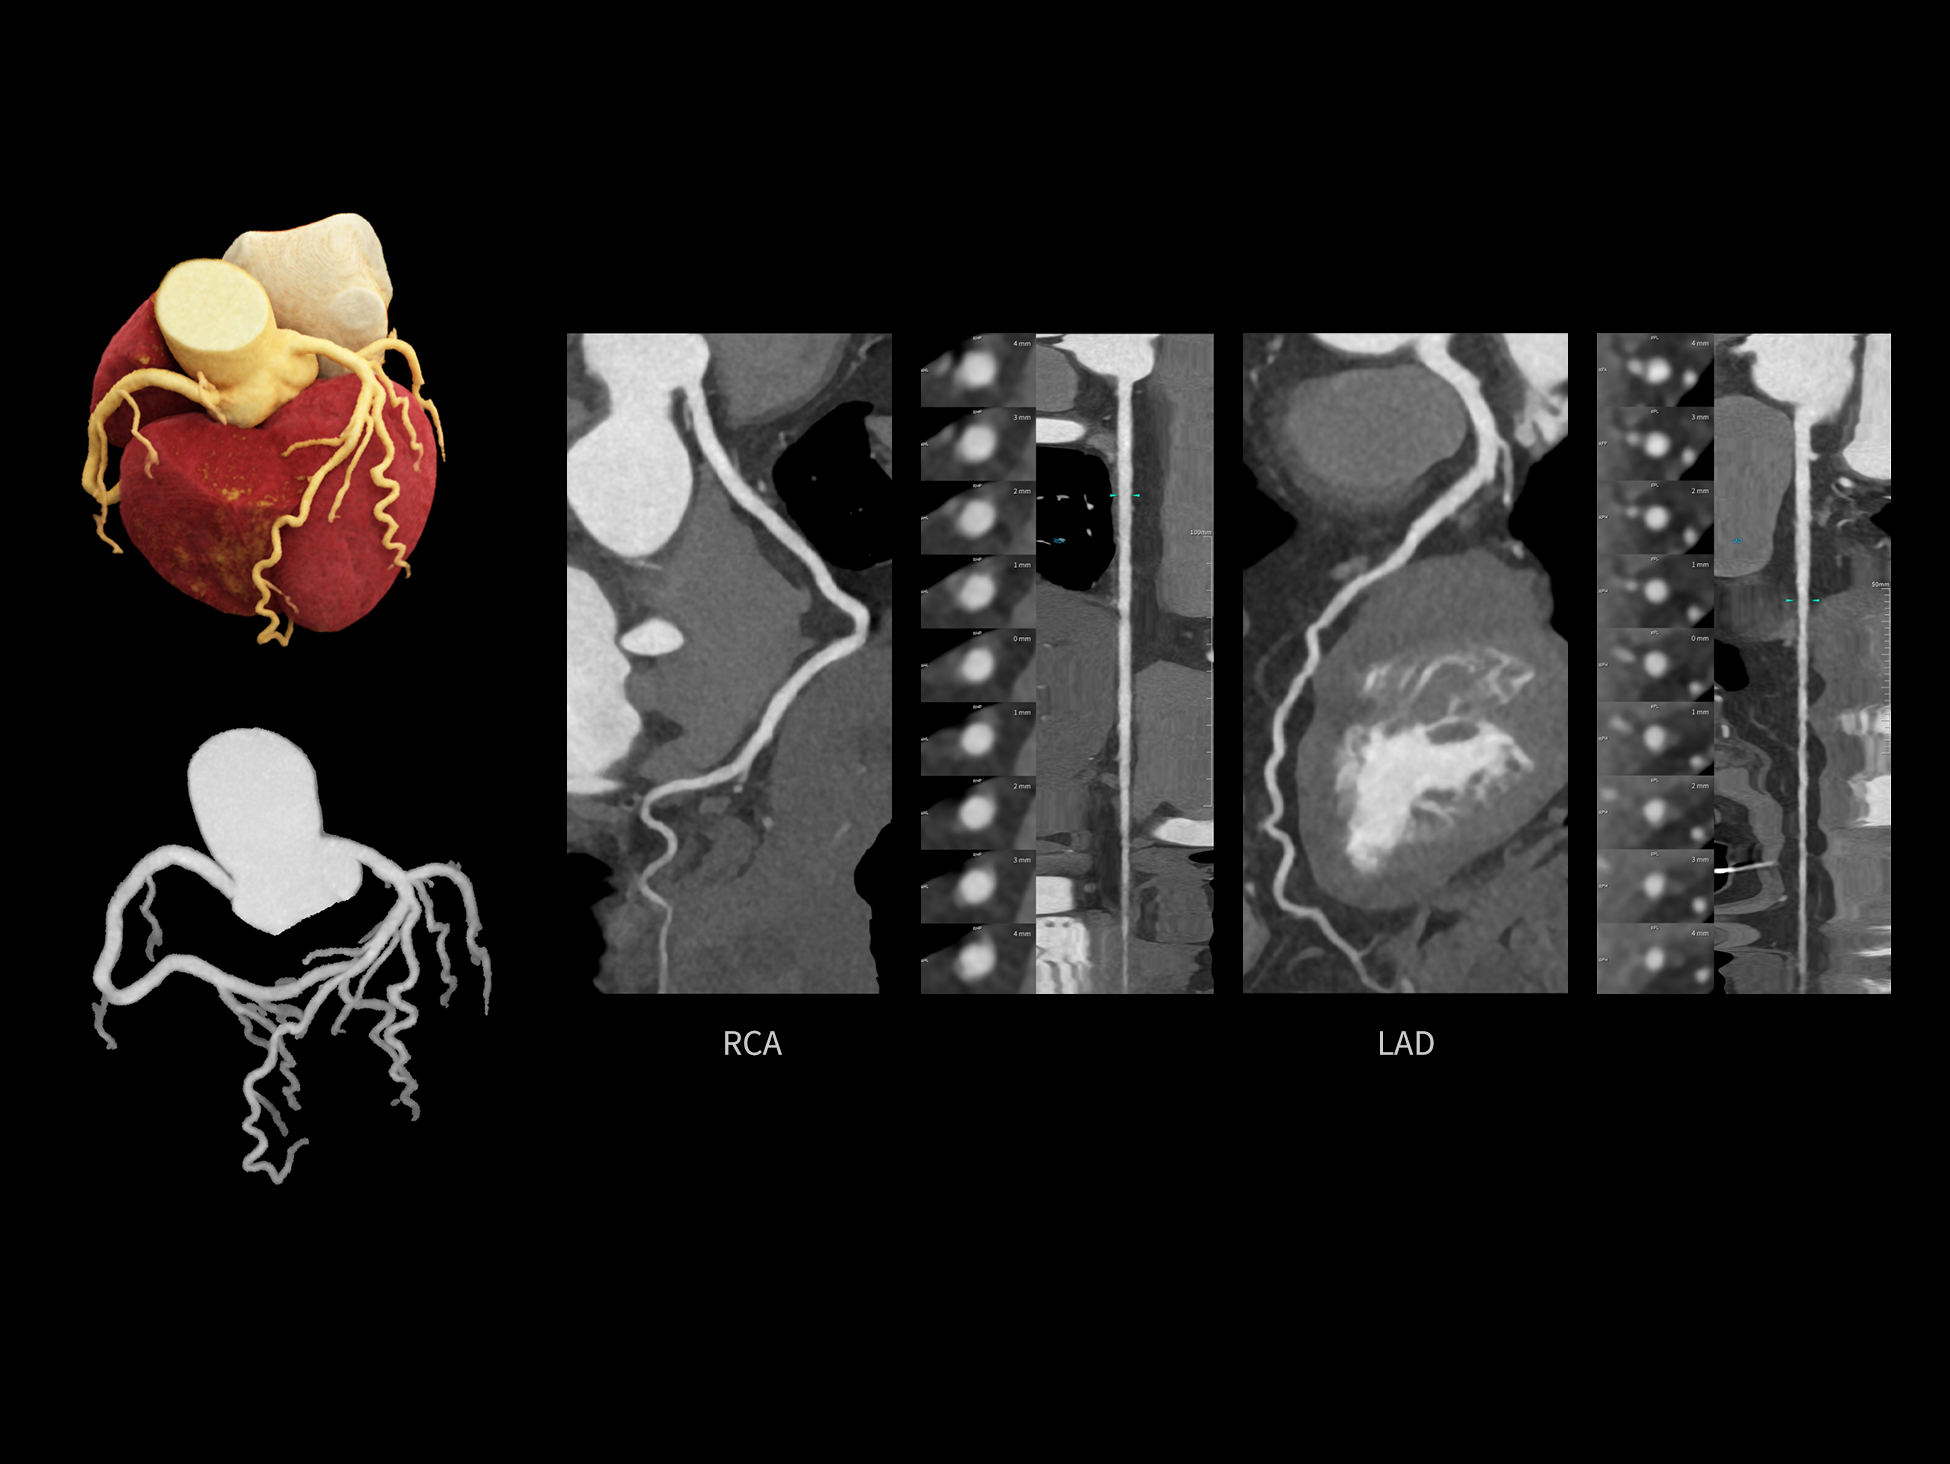

CardioCapture 2.0 通过“识别–追踪–建模–校正”的完整流程,精准分割心脏结构,动态追踪运动轨迹,并构建多时相运动场,最终实现冠脉、瓣膜、心肌及心室结构的同步校正,清晰洞见每一次心跳细微变化,真正将心脏动态掌握于毫秒之间。

CardioCapture 2.0 在目标时相前后重建多时相影像,通过深度学习网络精准提取冠脉中心线,进而建立时相间运动模型,实现对冠脉分段图像的精准运动校正。

CardioCapture 2.0 可对心肌、瓣膜及心室等结构进行同步运动校正。基于深度学习的心脏精细分割,实现了更完整的心脏全局信息提取,能有效抑制全心运动伪影,显著提升心脏细节的清晰度与诊断可靠性。

冠脉运动校正

全心结构运动校正